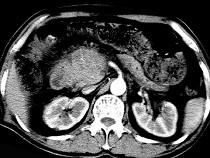

问题 男,50岁,黄疸进行性加重、腹部胀痛不适、食欲减退、体重减轻、上腹部可触及肿块,CT如图,最可能的诊断为()

选项 A.急性胰腺炎 B.慢性胰腺炎 C.胰头癌 D.腹膜后淋巴瘤 E.转移瘤

答案 C